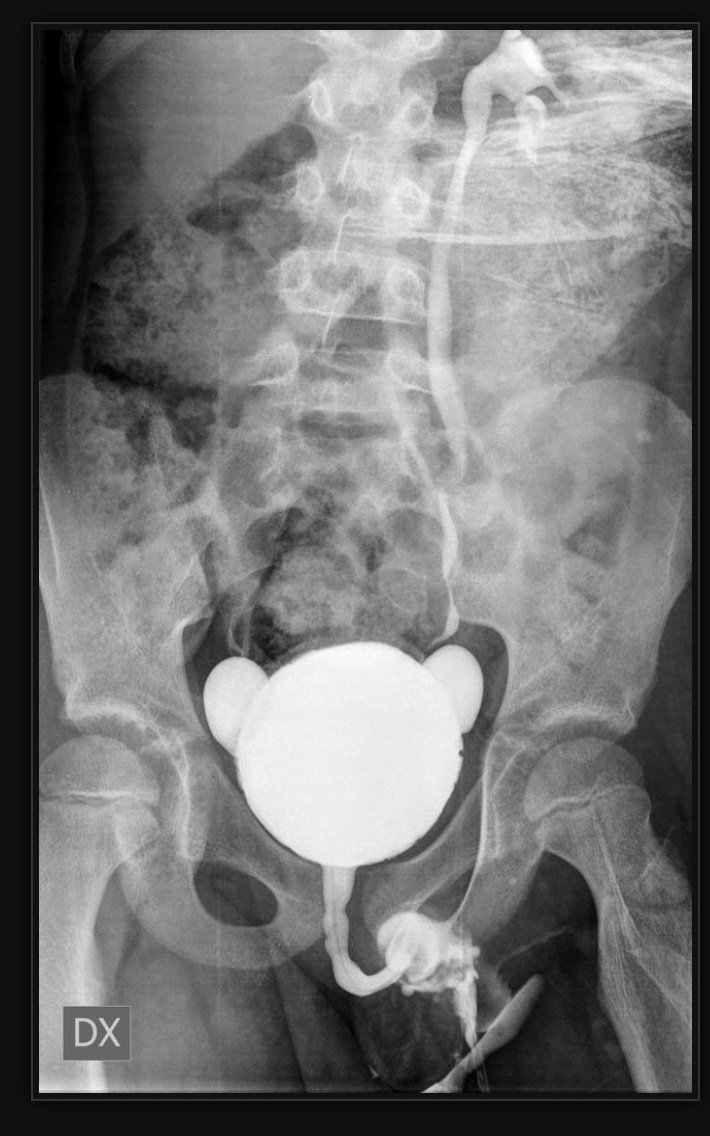

علامة حبة القهوة

Coffee bean sign

كدلالة على تضخم جزء من القولون sigmoid